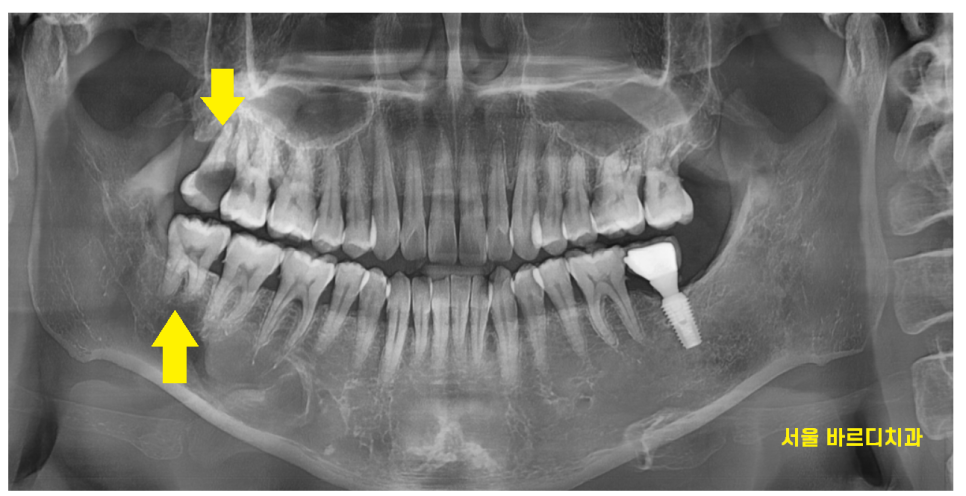

230701

반대로 누워있는 사랑니가

문제를 일으켜 불편하다? 뽑으셔야합니다.

(위에 사진은 사랑니가 뼈 안에 숨어있어요!)

벌어진 잇몸 아래로 음식물이 박혀

냄새가 나고 붓고

앞에 치아에 충치를 일으킬 것 같으면 뽑아야죠~

간혹 이런 사랑니가 큰 병원가서 뽑아야한다

얘기를 듣는데

신경관과 근접해 있어서

신경 손상이 있을 수 있어서 그렇습니다.